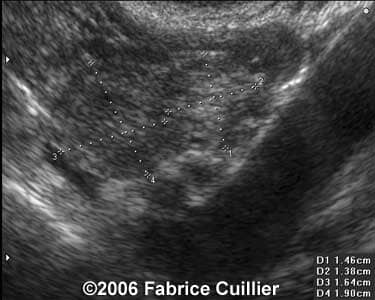

These are some cases of ectopic pregnancy (GEU) using the 2D and 3D scans.

Case 3